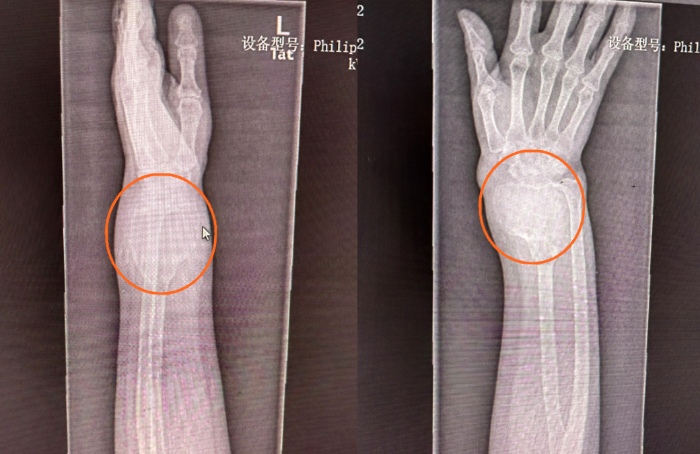

51歲的患者稅女士,一年前左前臂遠(yuǎn)端不明原因的出現(xiàn)一個包塊,她以為就是個軟組織包塊,沒太當(dāng)回事,包塊越來越大,到醫(yī)院拍片子一看,整個橈骨下段長達(dá)十多公分的骨頭上長的包塊已經(jīng)像個氣球一樣?!斑@個包塊是骨巨細(xì)胞瘤,是原發(fā)性骨腫瘤,長這么大,還是比較少見的,雖然是骨的良性病變,具有較強(qiáng)的侵襲性和轉(zhuǎn)移能力,會對骨質(zhì)有明顯的破壞性,需要進(jìn)行手術(shù)治療?!惫俪:歪t(yī)生看了片子跟患者交流。